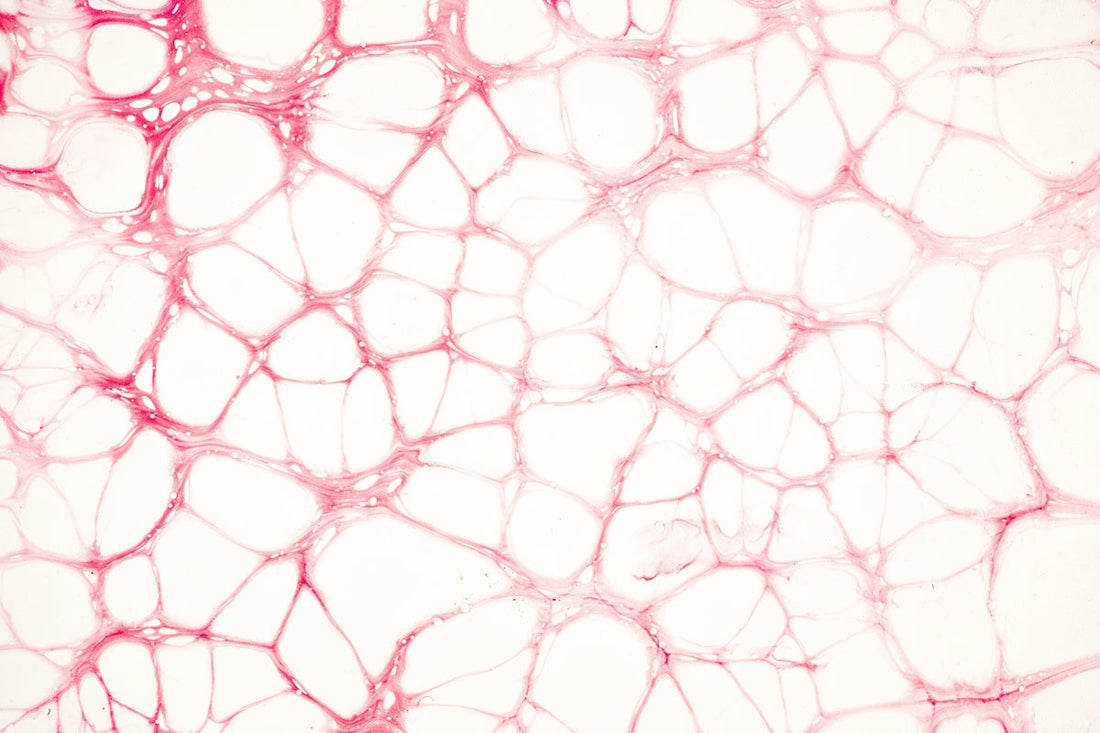

مرض رينود، الذي غالبًا ما يُستهان به، هو حالة تؤثر على تدفق الدم إلى أجزاء معينة من الجسم، عادةً أصابع اليدين والقدمين. عند التعرض للبرد أو الإجهاد، تضيق الأوعية الدموية، مما يؤدي إلى تحول لون المناطق المصابة إلى الأبيض أو الأزرق، والشعور بالبرد، والخدر. تؤثر عدة عوامل على ظهور مرض رينود، بما في ذلك التاريخ العائلي، والمهنة، والتعرض لمواد أو أدوية معينة.

- تغير لون الجلد: يتحول إلى اللون الأبيض، ثم الأزرق، نتيجةً لنقص تدفق الدم. ومع عودة تدفق الدم، قد يتحول لون الجلد إلى الأحمر وينتفخ.